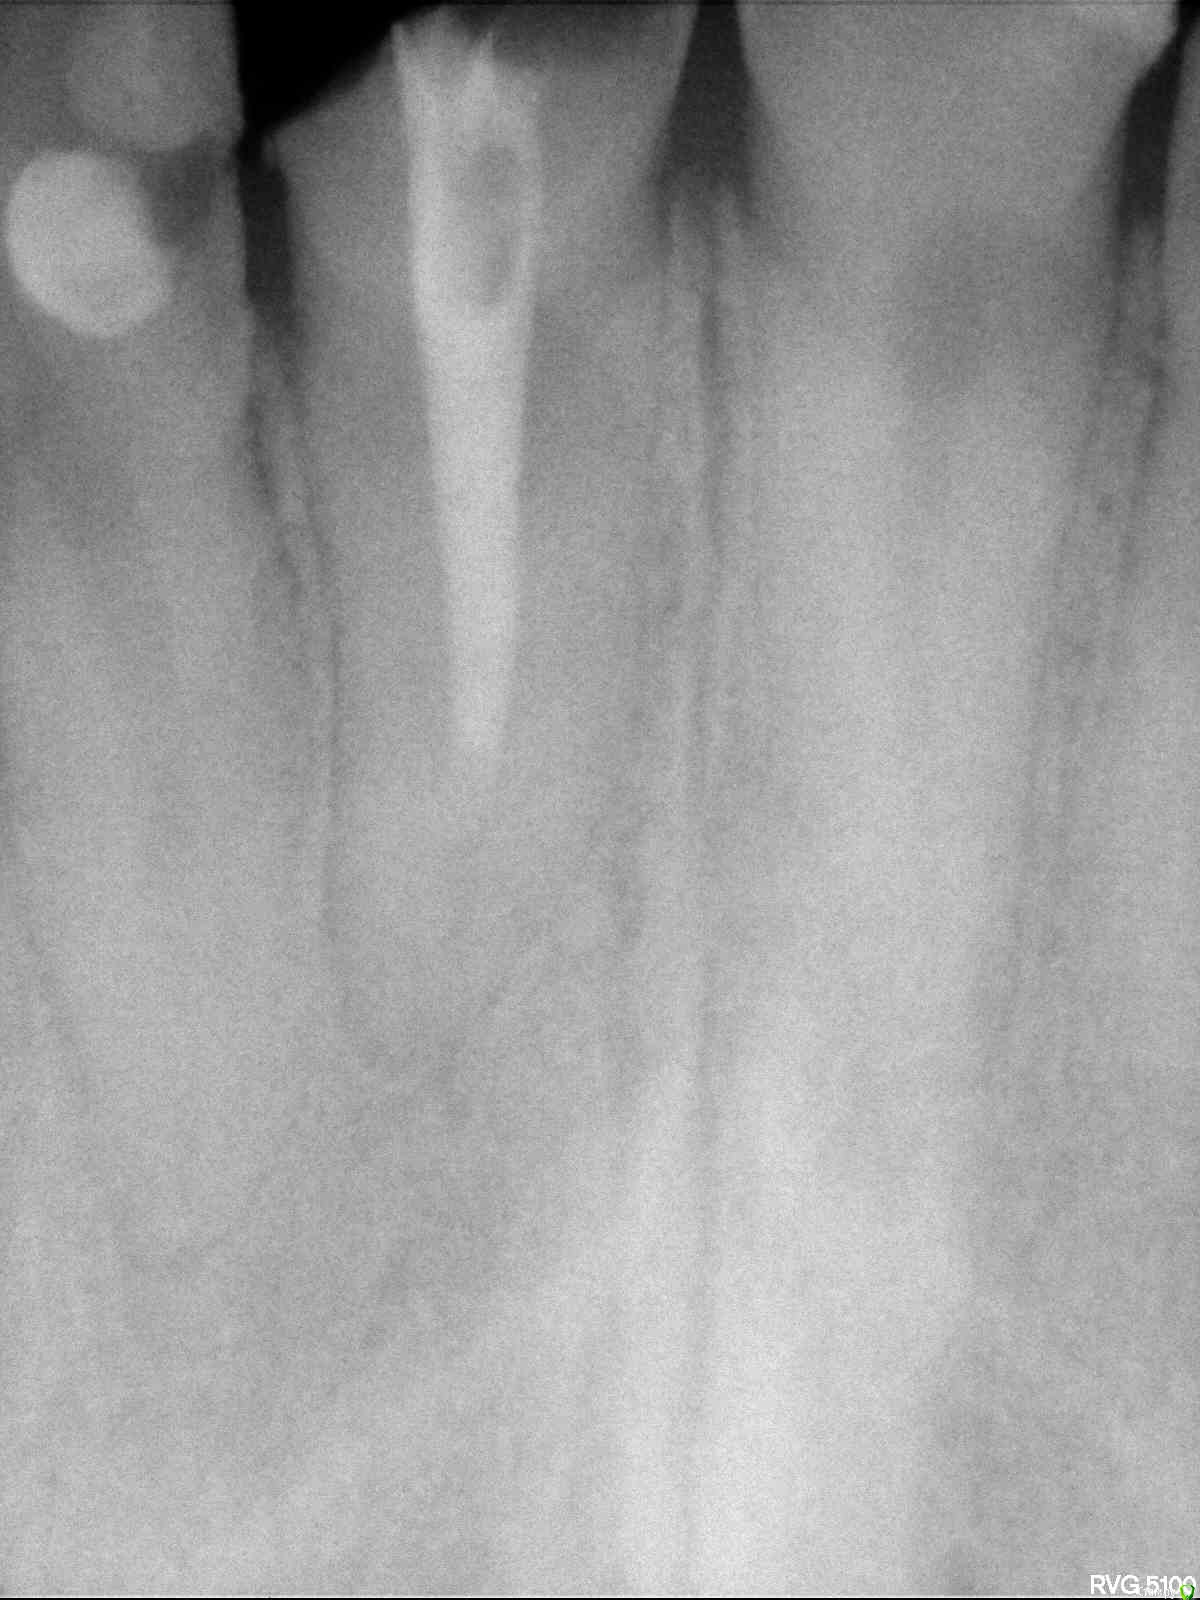

Vsergeev 20 Опубликовано 21 апреля, 2015 Поделиться Опубликовано 21 апреля, 2015 Добрый день.Сломался передний верхний левый зуб. 35 лет. Ходил в две клиники для консультации. Канал в зубе ранее пломбировали. На снимке видно, что канал до конца не заполнен пломбировочным материалом. Говорят, что периодонтит. Предложение первой клиники - вылечить, перепломбировать канал, сделать вкладку в корень и сверху коронку. Все устроило. И по цене доступно. Для уверенности и сравнения цен решил посетить еще одну клинику. Сказали, что лечить и ставить вкладку это без гарантии т.к. периодонтит. Лучше переплатить и ставить имплант. Есть ли практика, когда лечили корень, ставили коронку и потом приходилось выдергивать и всё же ставить имплант или вариант пролечиванием и сохранение корня может быть хорошим вариантом.Буду признателен за пояснения. Ссылка на комментарий

Vsergeev 20 Опубликовано 21 апреля, 2015 Автор Поделиться Опубликовано 21 апреля, 2015 снимок прикрепил Ссылка на комментарий

red_butler Опубликовано 21 апреля, 2015 Поделиться Опубликовано 21 апреля, 2015 Если судить только по снимку, зуб нужно перелечить и протезировать Ссылка на комментарий

St. Опубликовано 21 апреля, 2015 Поделиться Опубликовано 21 апреля, 2015 Я бы советовала попробовать побороться за свой зуб. По снимку смысл есть. Риск повторного воспаления есть, но в Вашем случае небольшой.А имплант всегда поставить успеете. Тем более, что импланты это тоже не панацея. Ссылка на комментарий